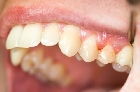

Cuando los niños pequeños son propensos a la caries dental, podrían perder los dientes de leche mucho antes de lo que deberían. También pueden sentir un cierto grado de incomodidad cuando se desarrollan en las cavidades profundas que empiezan a afectar a los nervios por encima de las raíces de los dientes y en estos casos es recomendado una pulpotomía.